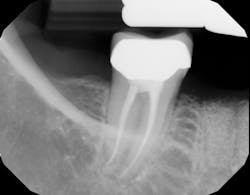

Because of this alveolar resorptive pattern after tooth extraction, bone grafting the extraction socket after tooth extraction procedures has become a solution that attempts to limit the amount of hard- and soft-tissue loss. There are many systematic reviews in the literature that compare the results of residual ridge dimension following tooth extraction after the use of a bone graft (with or without a membrane) versus extraction alone without grafting.7

Although there are many types of grafting products commercially available, choosing the right one may be difficult. An ideal bone graft substitute should be biomechanically stable; able to degrade within an appropriate time frame; exhibit osteoconductive, osteogenic, and osteoinductive properties; and provide a favorable environment for invading blood vessels and bone-forming cells.10